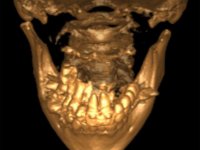

O estudo imagiológico para a colocação dos implantes, começou com a realização em laboratório de uma guia com dentes em sulfato de bário. Esta guia foi colocada em boca conjuntamente com marcas de referência coladas aos dentes, também em sulfato de bário. A guia foi estabilizada com cera mole. A TAC foi realizada com estas referências colocadas em boca. Após a realização da TAC foi feita uma impressão de arrasto em silicone. Esta impressão foi vazada a gesso em laboratório e posteriormente digitalizada. A digitalização do modelo com as referências foi sobreposta á imagem da TAC, permitindo uma planificação apurada na colocação dos implantes. Na planificação foi decidido colocar 2 implantes no local dos dentes 2.3 e 2.4 evitando-se a zona do 2.2 com pouco osso e o seio maxilar. Este estudo deu origem a uma guia cirúrgica que orientou a colocação dos implantes. Durante o período de osteo-integração a paciente utilizou a prótese removível rebasada com acondicionador de tecidos. A guia cirúrgica mostrou-se também útil na exposição dos implantes mostrando a sua localização precisa e orientando a incisão. A impressão definitiva foi realizada utilizando a técnica de moldeira aberta após eliminação do attachment. No laboratório foi confeccionada uma ponte metalo-cerâmica de 3 elementos com o elemento 2.2 em suspensão. A ponte após verificação e aprovação foi cimentada. A reabilitação apesar de pouco extensa (sem o elemento 2.6) mostrou-se capaz estetica e funcionalmente.